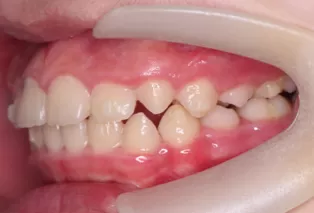

Photos intra-orales après traitement